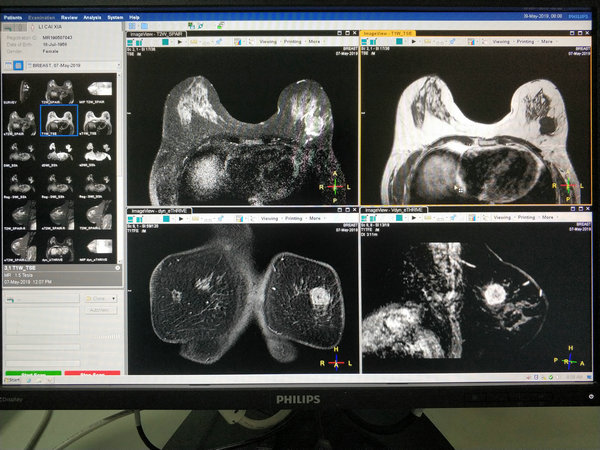

5月7日,磁共振科为即将去天津治疗的李女士完成了我院首例磁共振乳腺检查。乳腺磁共振的成功开展,为医院磁共振科又增加了一项新技术,同时能够明确乳腺疾病诊断,给患者提供最佳的诊治方案。

磁共振检查的软组织分辨率高、敏感性高,行乳腺磁共振检查,能三维立体的观察病变,不仅能够提供病灶的形态学特征,而且运用动态增强还能提供病灶的血流动力学情况,对乳腺疾病的诊断及病灶的检出达到了一个新高度,在国内外一些大城市已经广泛应用于乳腺癌的早期诊断。